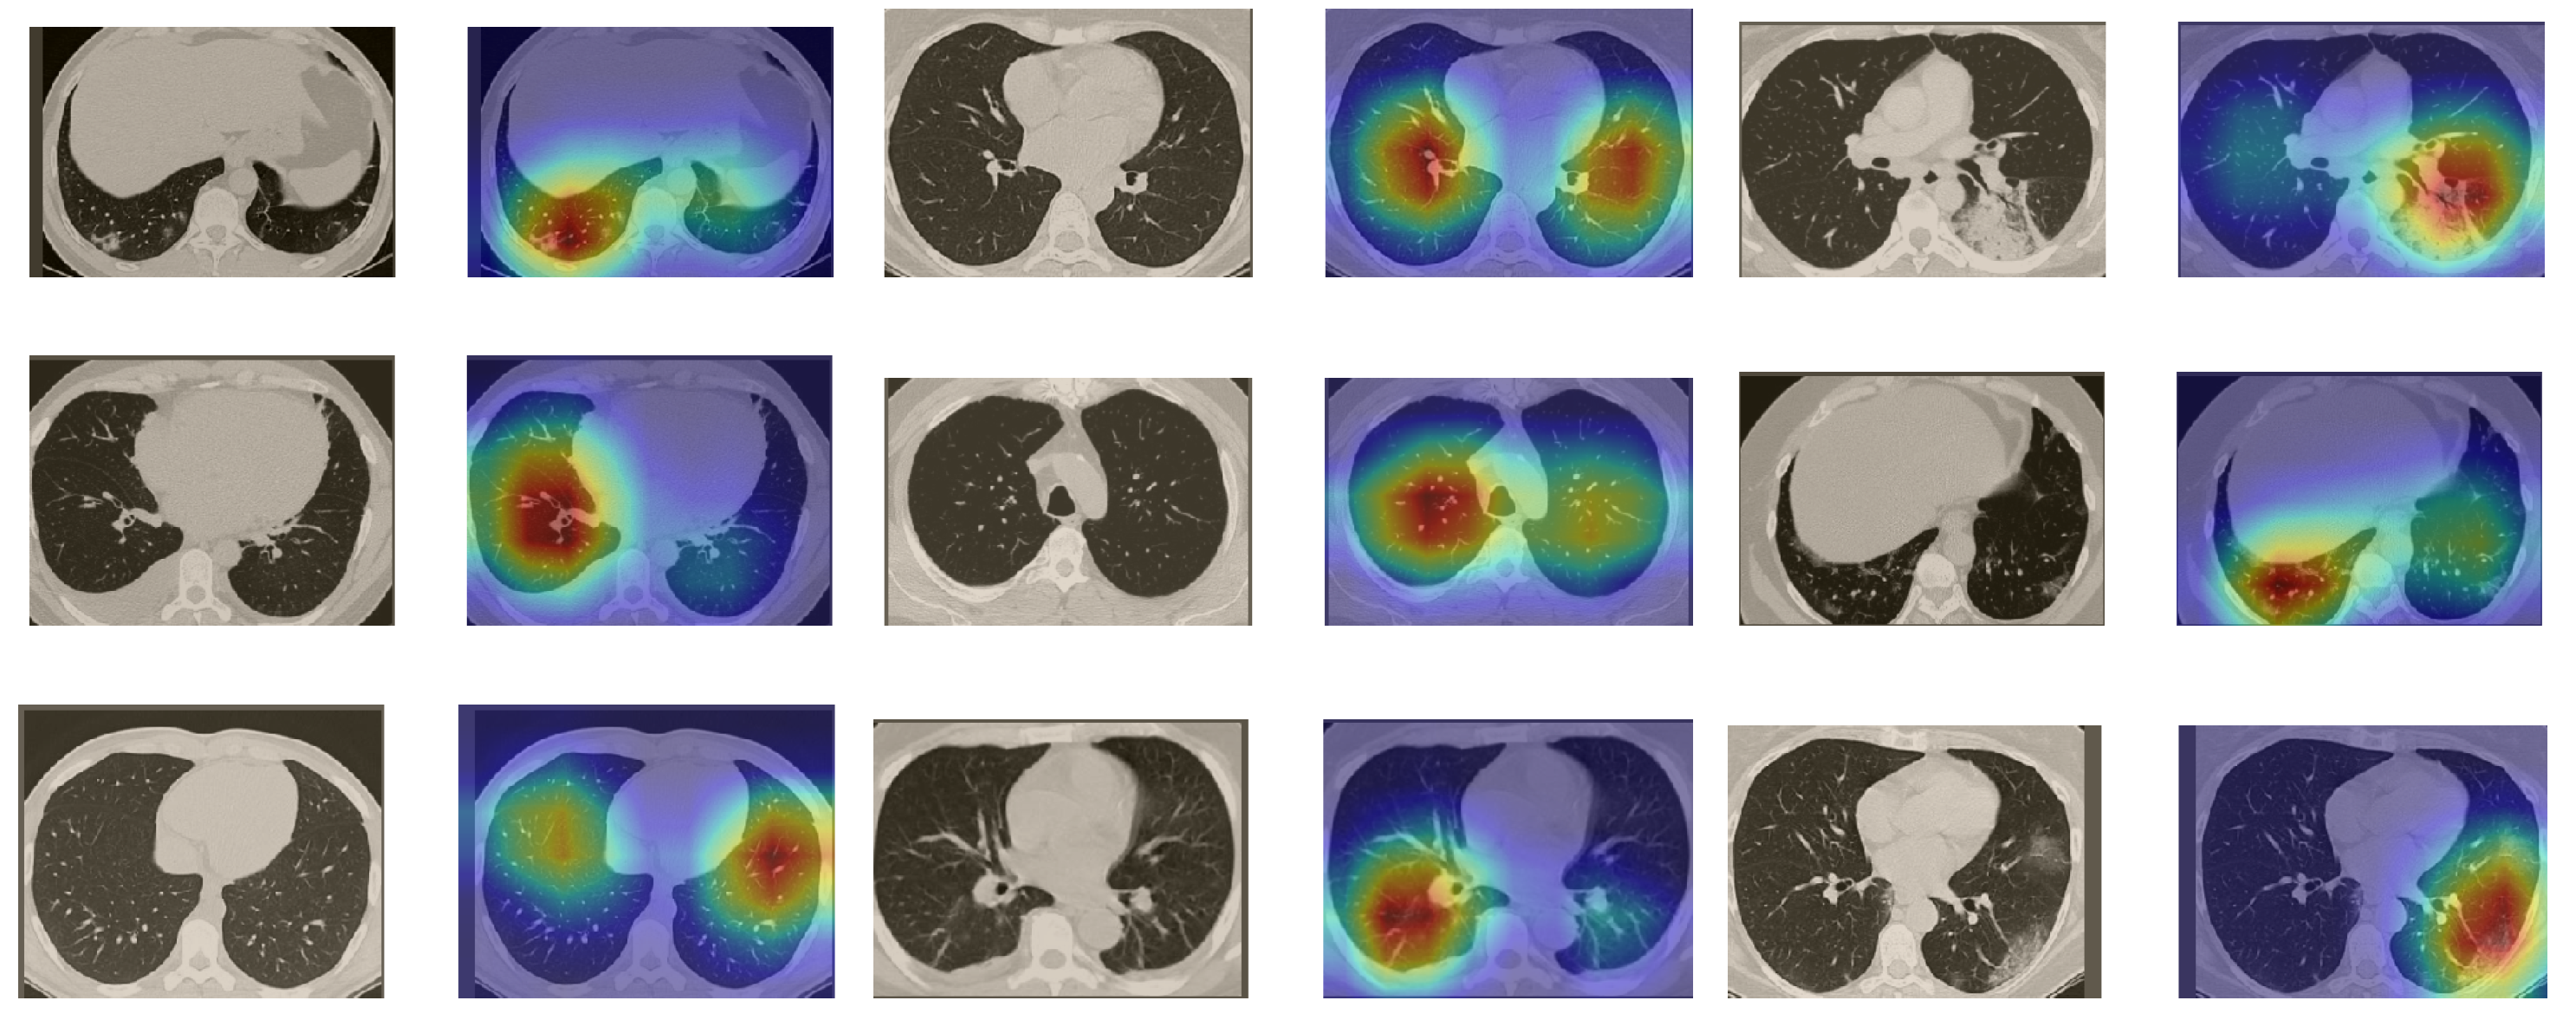

In a similar way, we considered classifying the test CT scans from the COVID-19 dataset by the DenseNet169 model, and highlight the important regions considered for predictions. We present samples of CT images and their localization maps in Figure 14. We can also see that our model is capable of detecting the COVID-19-related regions as annotated (small square in some images) by expert radiologists.

Figure 14.

Grad-CAM visualizations for sample CT images from the COVID19-CT dataset. Our DenseNet169 model correctly classified them as COVID-19 cases and highlighted the most relevant regions, as shown in the corresponding localization maps.